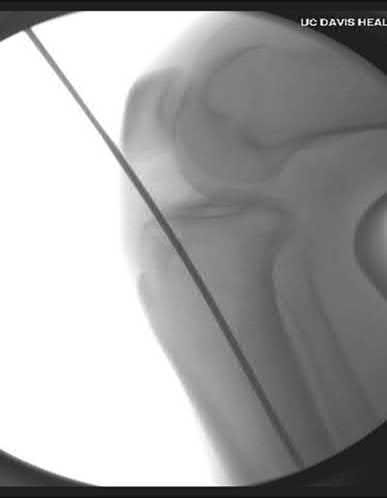

Figures A through D show consecutive 2.00 mm sagittal CT reformats demonstrating a small coronoid fracture fragment which was addressed with suture fixation.

The clinical presentation is consistent with a coronoid tip fracture. This fracture pattern is associated with a radial head fracture and posterolateral ulnohumeral dislocation - together making up the terrible triad injury.

A terrible triad injury is the result of a valgus and supination injury and involves posterolateral elbow dislocation or lateral collateral ligament injury, radial head fracture, and fracture of the coronoid process. The elbow may dislocate postero-laterally with the anterior bundle of the MCL intact, but if the MCL is injured it is typically the last structure to fail. The coronoid fracture is typically a small fragment isolated to the tip. This is a result of a posteriorly directed force driving the coronoid into the trochlea prior to posterior elbow dislocation. CT scan is a useful modality when small or comminuted fragments are difficult to visualize on plain radiographs.